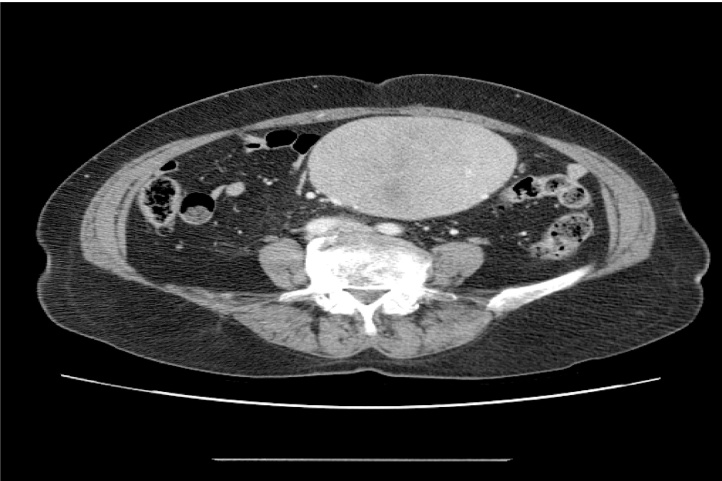

A 69-year-old woman was admitted to our hospital because of abdominal pain and a periumbilical palpable intra-abdominal mass for 20 days. Physical examination revealed a huge, well circumscribed, firm palpable mass in the left periumbilical area of the abdomen. The vital signs of patient were stable. Carcinoembryonic antigen(CEA) and carbohydrate antigen 19-9(CA19-9) were within normal limits. Computed tomography (CT) of the abdomen and pelvis showed a large solid mass (long diameter: approximately 12 cm) with well-defined borders in the small bowel mesentery. (Fig. 1).

Fig. 1.

Abdominal CT shows a large solid mass with well-defined borders in the small bowel mesentery.